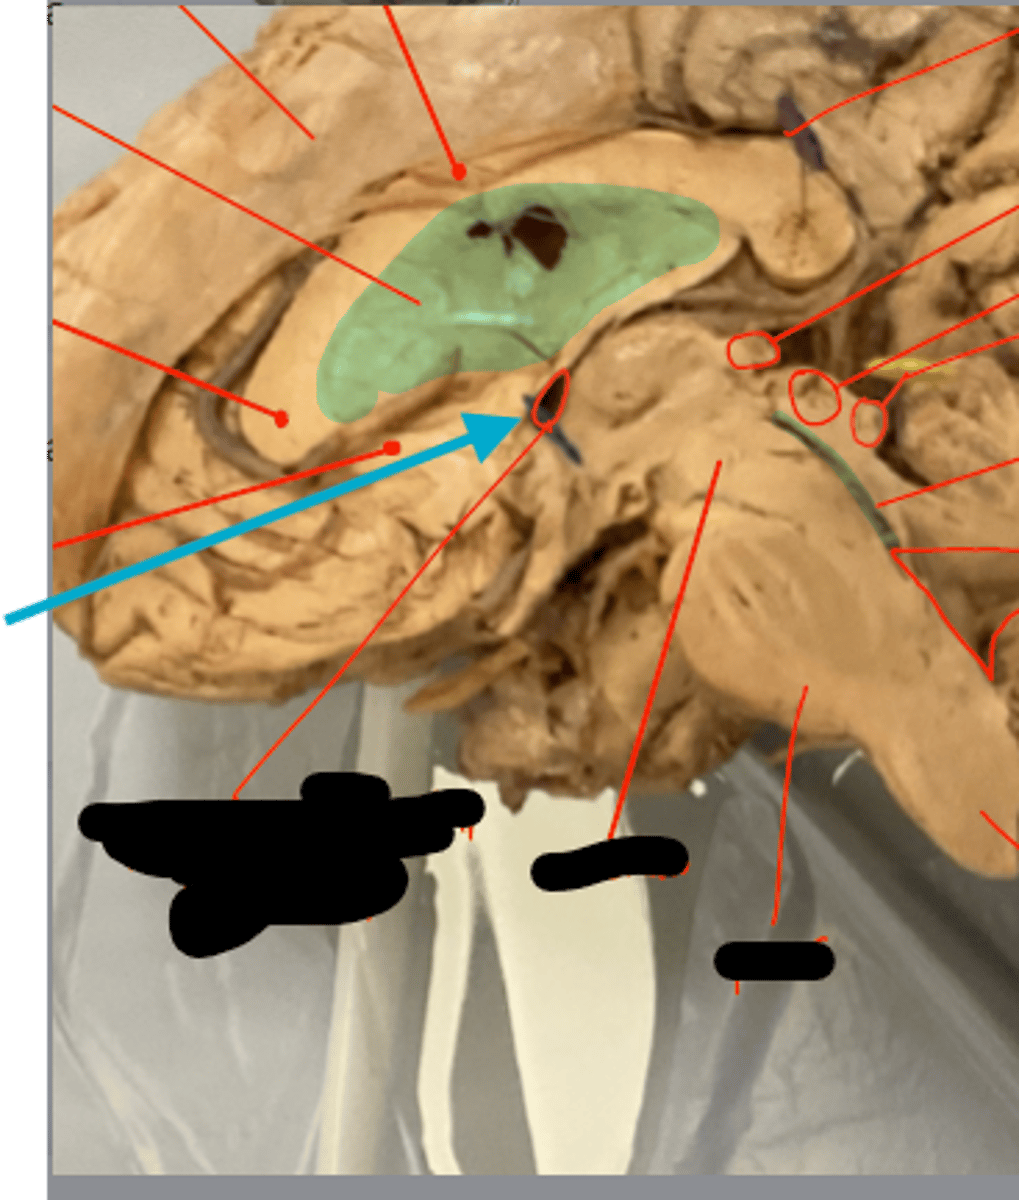

What is the blue arrow pointing at?

what structure is the blue pin in?

What is number 50 or the blue dot?